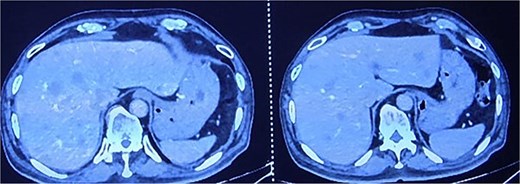

(1) Contrast-enhanced computed tomography (CECT) of the abdomen and pelvis demonstrated enhancing circumferential wall thickening involving the anal canal and lower rectum, with obliteration of the intervening fat plane between the tumor and the prostate. Multiple peripherally enhancing lesions were identified in both hepatic lobes, suggestive of hepatic metastases (Fig. 2a). Several pleural-based pulmonary nodules were seen bilaterally, consistent with metastatic deposits (Fig. 2b).

CECT abdomen and pelvis showing hepatic metastasis and pulmonary metastasis.